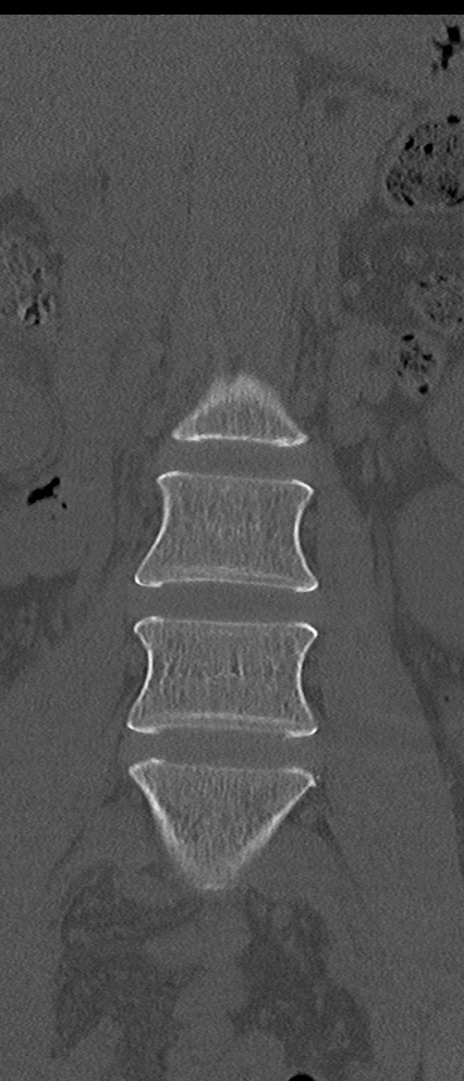

【整形】TIPS症例4 腰椎CT(冠状断像)

腰椎CT